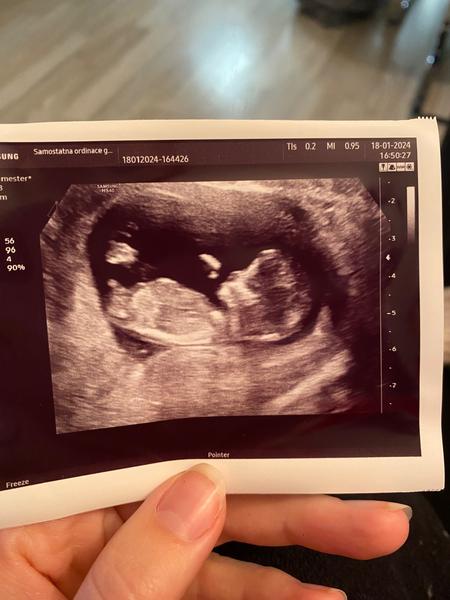

Pohlaví dítěte. Je možné jej odhadnout?

dokázal byste z přiložené fotky odhadnout pohlaví dítěte?

posuzovat pohlaví z jednoho snímku a v prvním trimestru má své velké limitace a vždy je to jen hrubý odhad a dojem. Doporučuji vyčkat na ultrazvuk ve 20. týdnu, tam to bývá již jednoznačné. 🙂